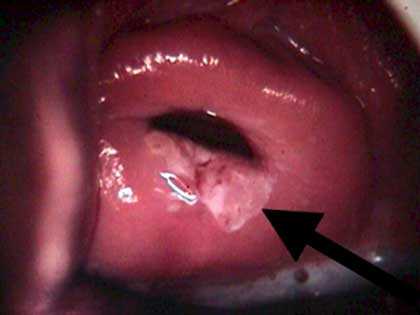

Фотогалерея: как выглядит шейка матки через кольпоскоп

- Простая обзорная кольпоскопия ограничивается обычным осмотром шейки матки без применения каких-либо индикаторов

- Шеечный эпителий под воздействием уксусной кислоты белеет

- При пробе Шиллера здоровые клетки окрашиваются в тёмно-коричневый цвет